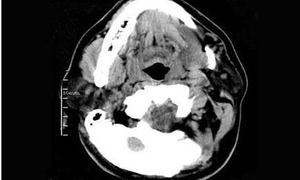

口舌痰包,中医病名。是因痰湿流聚于口舌所致。以口腔或舌下出现圆滑柔韧囊肿为主要表现的痰包类疾病。本病多见于西医学所指舌下腺囊肿及口腔粘液腺囊肿。

3、发生于舌下者,肿物多位于一侧,呈淡蓝色或淡黄色,表面光滑,如鸽蛋大小,触之不痛,有波动感,穿刺有蛋清样液体。痰包过大时,可将舌体推向对侧。